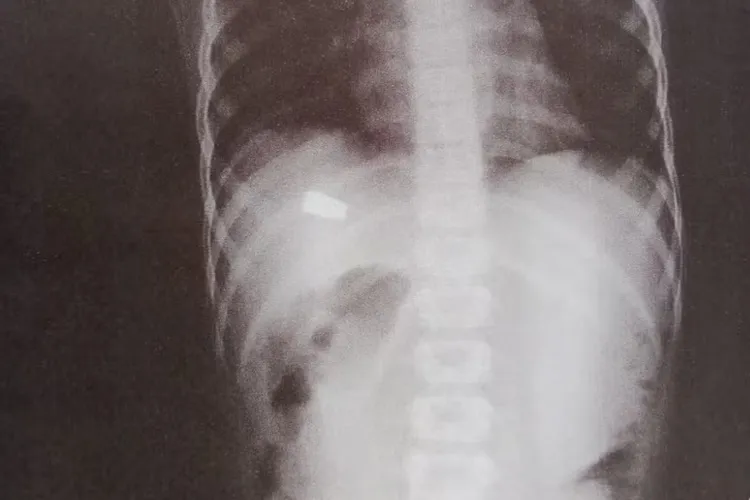

Criança de 8 anos é baleada enquanto brincava na casa da madrinha em Salvador Foto: Reprodução/G1

Uma criança de 8 anos foi baleada enquanto brincava na casa da madrinha, no domingo (4), no bairro de Mussurunga, em Salvador. Segundo informações da família, o menino contou para a madrinha que estava sentindo dor no abdômen após ser atingido por um pedaço de telha da casa. A mulher o levou à Unidade de Pronto Atendimento (UPA) do bairro ao perceber que a criança tinha um sangramento. De acordo com o G1, na unidade de saúde, onde a criança fez um exame de raio-x, os médicos descobriram que ela tinha sido atingida por um tiro. A Polícia Civil investiga o caso como tentativa de homicídio. A suspeita é de que a criança tenha sido vítima de bala perdida. A madrinha da criança contou que a casa dela fica na parte baixa da rua e o tiro pode ter atingido o telhado do imóvel. A mulher contou à polícia que ouviu barulho de disparos, mas que parecia distante. Lúcida, a criança foi transferida para o Hospital Geral do Estado (HGE), onde está internada na Unidade de Terapia Intensiva (UTI).